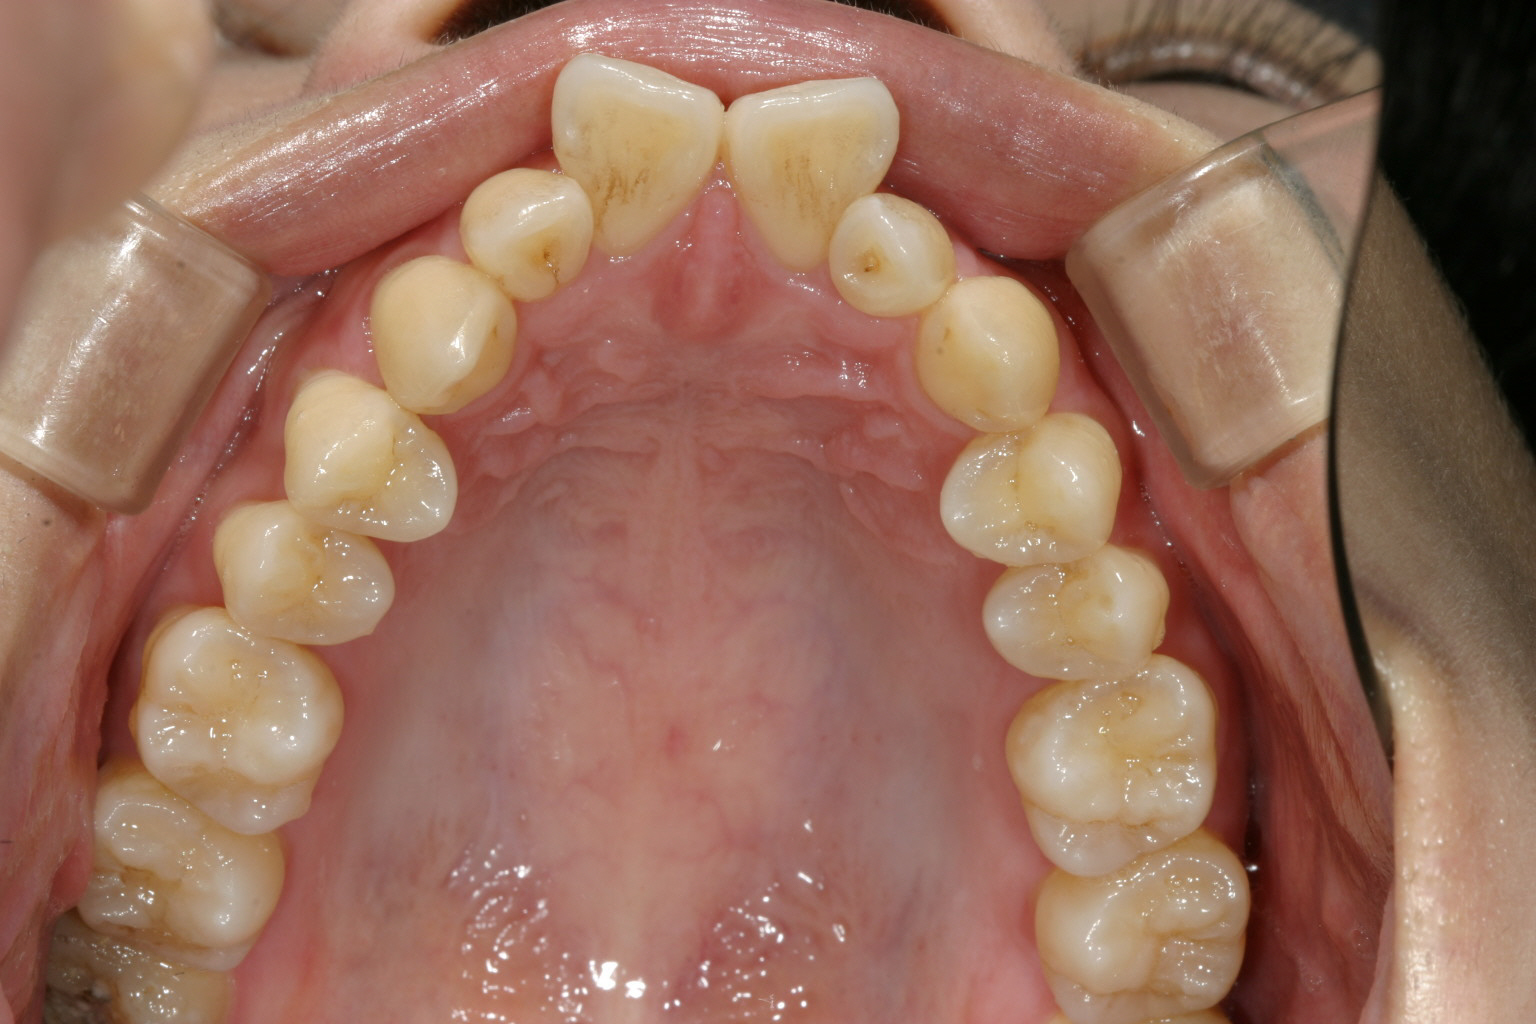

かなりヘビーな翼状捻転です。

綺麗なアーチに改善いたしました。